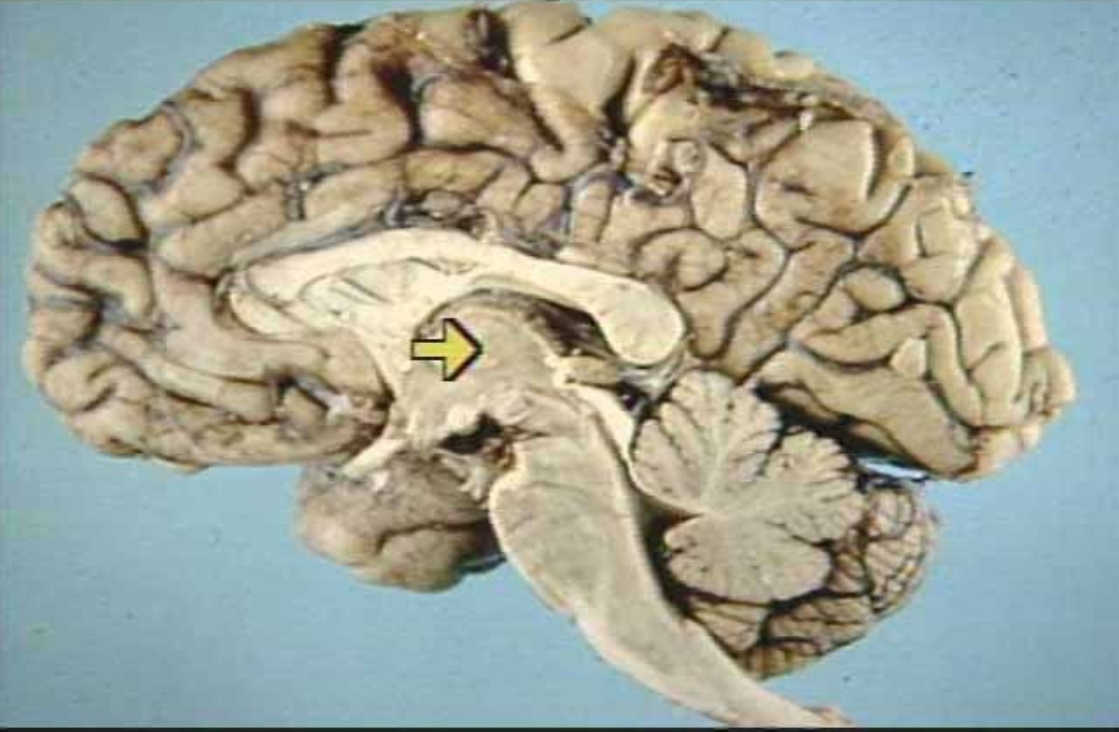

What is the arrow pointing at?

Hippocampus